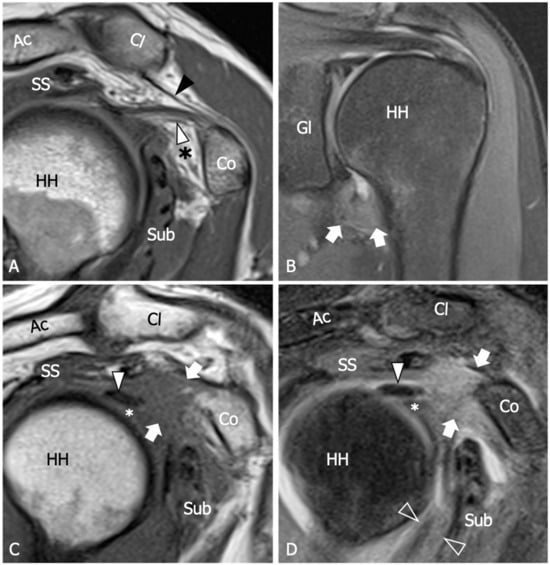

Figure 3.

Adhesive capsulitis, spectrum of MRI findings. (A) Sagittal tSE T1-weighted MRI scan from a 42 year old woman with a three-month history of shoulder pain demonstrates mild thickening of the coracohumeral ligament (white arrowhead) and initial effacement of the subcoracoid fat triangle (asterisk) by hypointense synovium. Black arrowhead, coracoacromial ligament. (B) Coronal tSE Proton Density MRI scan from a 68 year old woman with recent onset of pain and progressive limitation of glenohumeral ROM shows a marked thickening of the inferior capsule (arrows), which appears edematous and demonstrates increased signal intensity in fluid-sensitive sequences. (C) Sagittal tSE T1-weighted and (D) Sagittal tSE fat-suppressed T2-weighted MRI images from a 70 year old male with a one-year history of severe limitation of active and passive shoulder motion demonstrate complete obliteration of the subcoracoid fat triangle by synovial tissue (arrows), which is also extended underneath the long head of the biceps tendon (arrowhead) in the area of the pulley (asterisk). The coracohumeral ligament appears embedded by the synovium. Note severe thickening and hyperintensity of the anteroinferior capsule (outlined arrowhead). Ac, acromion; Cl, clavicle; Co, coracoid; SS, supraspinatus; Sub, subscapularis; GL, scapular glenoid; HH, humeral head.

The thickening of the rotator interval and coracohumeral ligament are considered specific signs, although poorly sensitive, of AC. Various cut-off points were proposed in the past, and the optimal value is still a matter of debate. Mengiardi et al. found that a rotator interval capsule thickness ≥7 mm had a specificity of 86% but only a sensitivity of 64% [54]. Similarly, they reported that a coracohumeral ligament thickness ≥4 mm had high specificity (95%) but lower sensitivity (59%). In another study by Jung et al., it was suggested that a rotator interval thickening of over 6 mm on sagittal oblique proton-density images may correlate with the patient’s range of rotational motion [55]. Synovial proliferation around the rotator interval can be observed as capsule thickening with intermediate to low T1 signal intensity, hyperintense signal on fluid-sensitive sequences, and enhancement after contrast administration. While the synovial obliteration of the triangular fat pad inferior to the coracohumeral ligament has been identified as a sign with high specificity (100%), its sensitivity remains poor (32%) [54]. Referred to as the “subcoracoid triangle sign”, the obliteration of the subcoracoid fat pad has been more frequently observed in early clinical stages 1 and 2 of AC [56]. The visibility of this sign is optimal on sagittal oblique images and can be easily evaluated using conventional MRI techniques, where it appears hypointense relative to subcutaneous fat on T1-weighted images.

Several research studies have shown that hyperintensity and thickening of the inferior shoulder capsule are indicative of AC. In particular, hyperintensity in the axillary pouch/inferior glenohumeral ligament complex on MRI using non-arthrography T2-weighted fat-suppressed sequences demonstrated high sensitivity (85.3–88.2%) and specificity (88.2%), and low variability among different observers with a kappa value of 0.85 [57]. Regarding inferior capsule thickness, a first MRI study with a limited number of participants evidenced that when the measurements of the joint capsule in the axillary recess exceed 4 mm on T1 oblique coronal MR images, it suggests the diagnosis of AC with a sensitivity of 70% and a specificity of 95% [58]. In Jung et al.’s study, performed with conventional MRI, a threshold value of 4.5 mm in axillary recess capsule thickness measured on T1 oblique coronal images demonstrated the greatest diagnostic accuracy for AC, with a sensitivity, specificity, and overall accuracy of 91%, 90%, and 90%, respectively [55]. Other studies have shown that the thickness of the axillary recess is related to the clinical stage. Sofka et al. found a mean axillary pouch thickness of 7.5 mm for stage 2, also demonstrating a statistically significant correlation between the hyperintense signal of the capsule on proton density sequences obtained with conventional MRI and this clinical stage [56]. Contrary to the claim that MRA may have some advantages in measuring inferior capsular thickness, it is important to consider potential risks and complications associated with this technique, including hemorrhage and septic arthritis. Moreover, the sensitivity and specificity of inferior glenohumeral thickening on MRI were not significantly different from those on direct MRA found in a recent meta-analysis [52]. Overall, despite the potential of MRA in disclosing ancillary findings, such as leakage of contrast agent anterior to the medial margin of the scapula, reduced distension of the axillary recess, pseudo-synovitis over the cranial border of the subscapularis tendon and the biceps anchor, and widening of the subscapular recess [1] (Figure 4), the intra-articular injection of contrast agents appears unjustified in patients with AC.